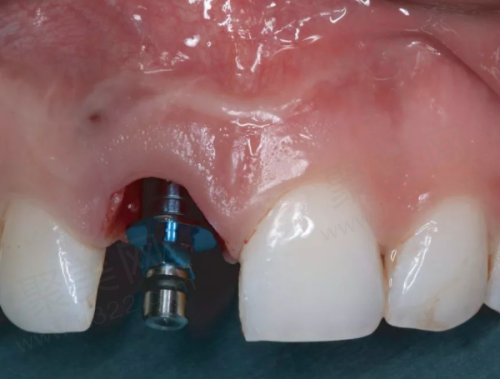

宋起医生在种植手术中操作熟练。他能够精细地将种植体植入到合适的位置,并且在手术过程中尽量减少对患者口腔组织的损伤。他的手术风格稳健,注重细节,每一个步骤都严格按照规范进行,以确保种植手术的顺利进行。

在种植牙手术过程中,宋起医生的操作精细。他会使用精良的种植设备和技术,确保种植体能够正确地植入到预定的位置。他对手术的每一个环节都严格把控,从切口的设计到种植体的植入深度和角度,都力求做到理想。在植入种植体后,他会仔细检查种植体的稳定性,确保其能够与牙槽骨良好地结合。